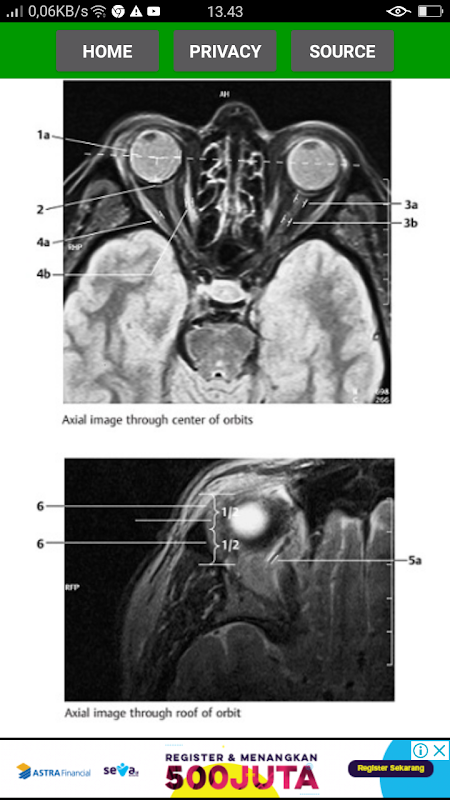

Diagnostic radiology about Normal Findings in CT Brain and Brain MRI

The key for any beginning radiologist who wishes to recognize pathological findings is to first acquire an ability to distinguish them from normal ones. This outstanding guide gives beginning radiologists the tools they need to systematically approach and recognize normal MR and CT images.

* Reference-quality images from the author's own teaching files show all standard normal findings as seen in CT and MRI